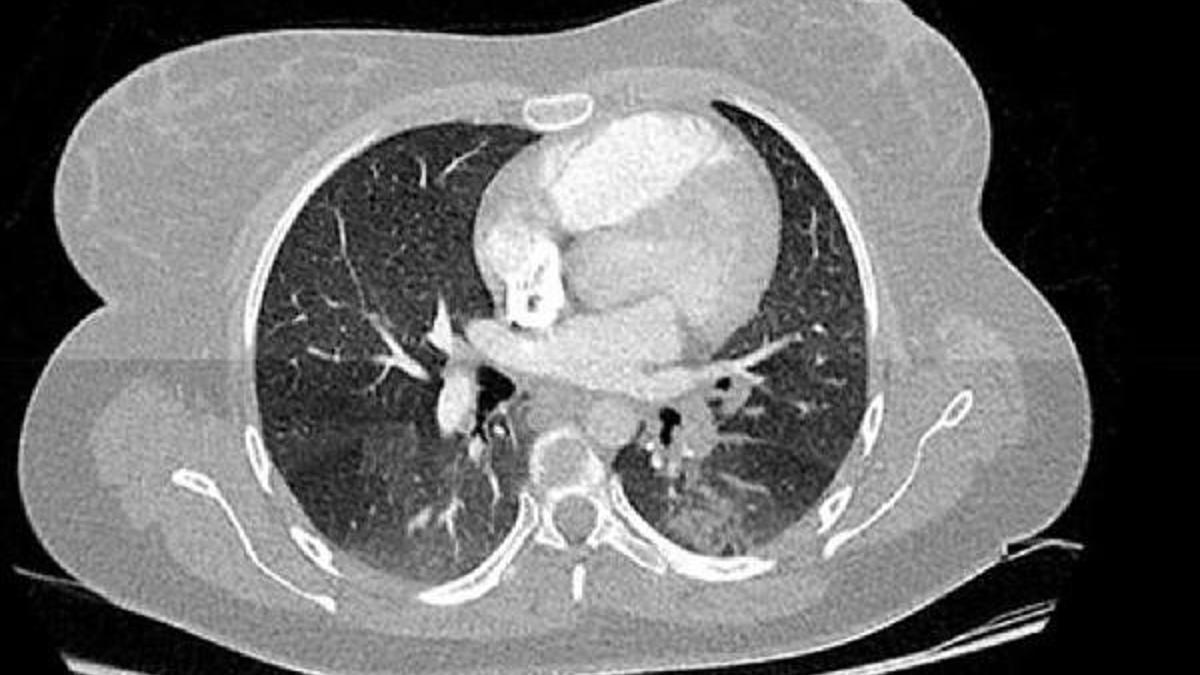

Koronavirusun Akcigere Verdigi Zarar Goruntulendi

www.yenicaggazetesi.com.tr

Corona Virusun Insan Vucudundaki Etkisi Boyle Goruntulendi

Coronavirusun Akcigerde Nasil Yayildigi Goruntulendi

Iste Koronavirusun Akcigerlerde Yol Actigi Hasar Dunyadan Haberler

www.cnnturk.com